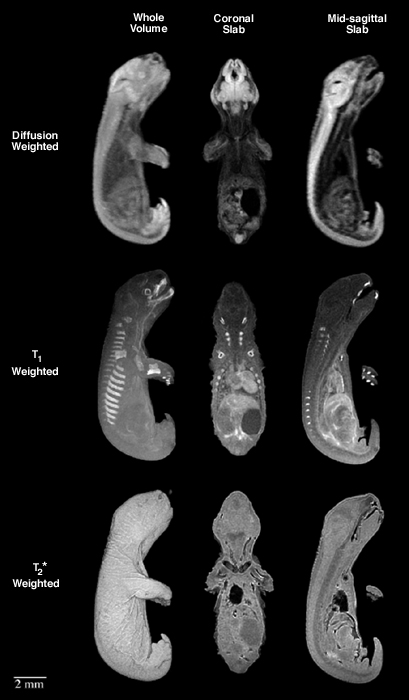

Magnetic resonance imaging of the South American Opossum. Three distinct imaging schemes demonstrate the different information available depending on the image acquisition settings.

MRI images of opossum fetus